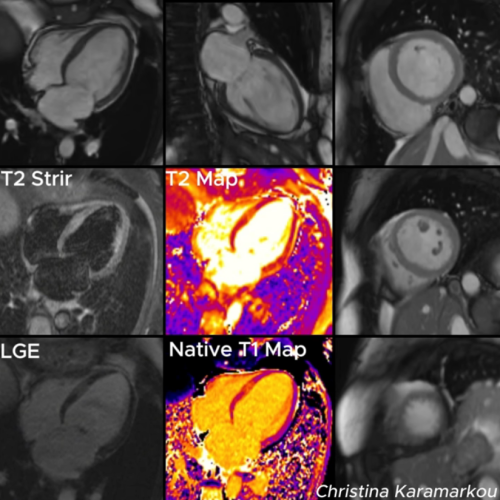

Diagnosis and Treatment of Rare Cardiac Conditi...

Mrs. Lim, a 58-year-old Malaysian patient, was initially misdiagnosed with idiopathic pulmonary arterial hypertension (IPAH). After a comprehensive diagnostic evaluation in Beijing, she was correctly diagnosed with a double-chambered right...